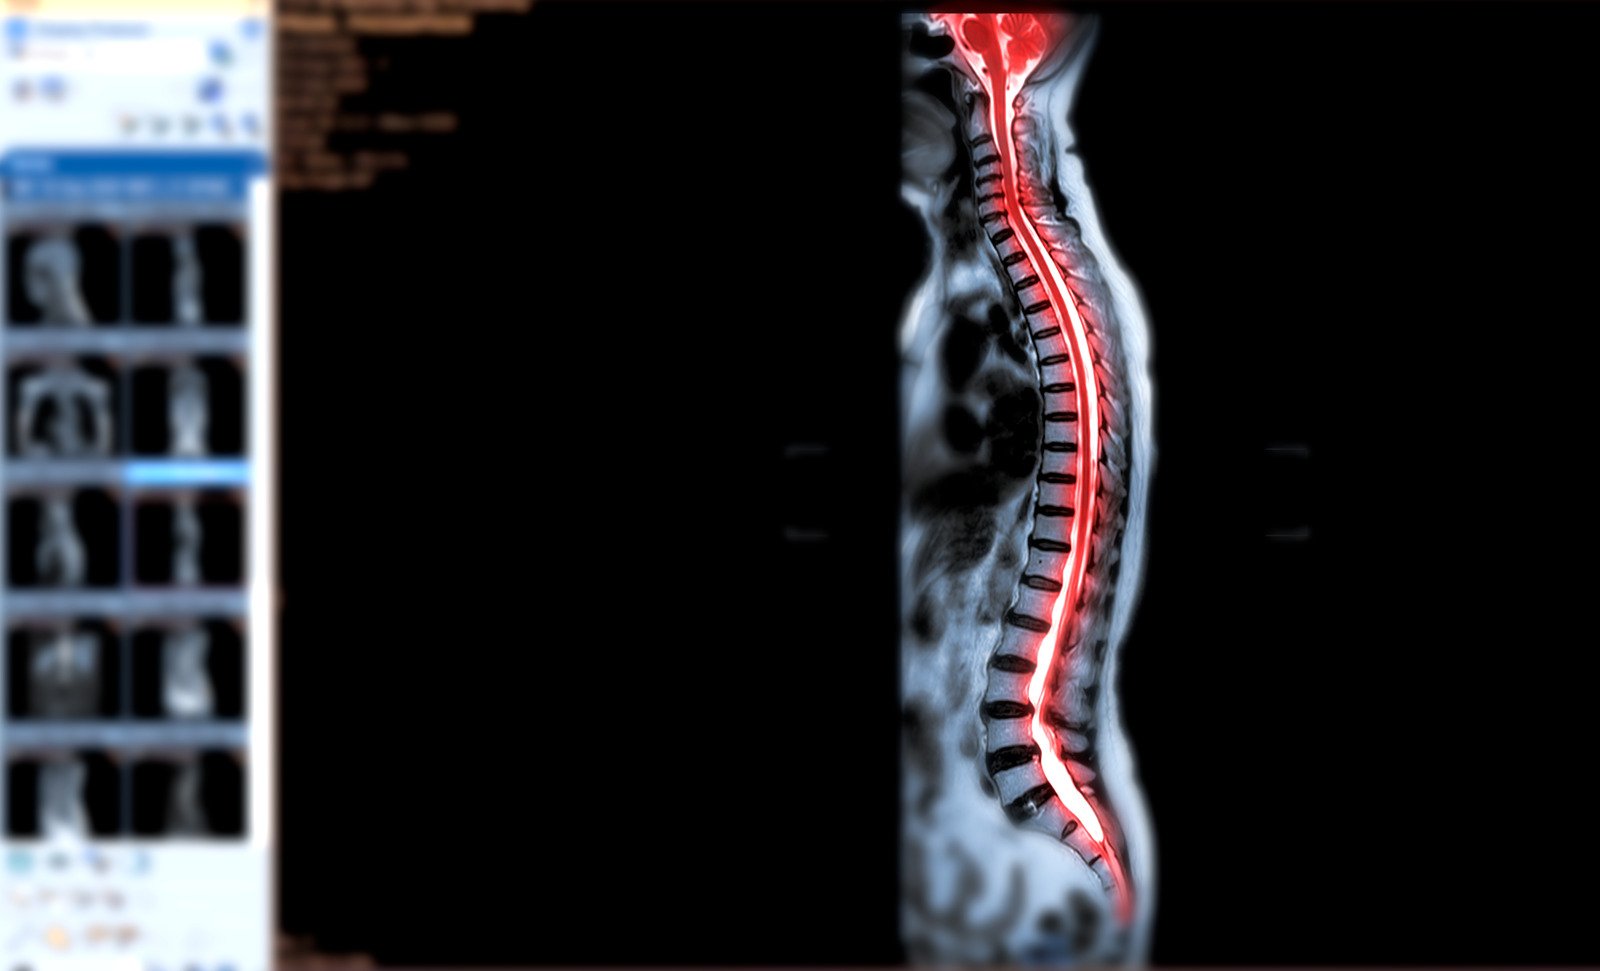

척수 신경 압박(Spinal Cord Compression): 원인, 증상, 치료 및 예방

✅ 척수 신경 압박(Spinal Cord Compression)은 척수를 둘러싼 구조(뼈, 디스크, 종양 등)가 척수를 압박하면서 신경 기능에 영향을 미치는 상태를 의미합니다.

✅ 목(경추), 등(흉추), 허리(요추) 등 어디에서나 발생할 수 있으며, 압박 정도에 따라 심각한 신경 손상을 초래할 수 있습니다.

📌 MRI 검사가 척수 신경 압박의 원인을 정확하게 파악하는 데 가장 효과적입니다.